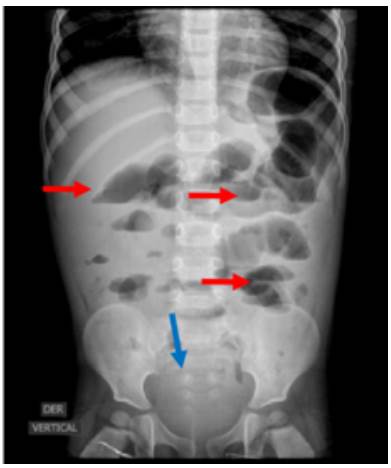

Plain abdominal x-ray (red arrows). Absence of distal gas (blue arrow); air-fluid levels (red levels).

Fig 1: Plain abdominal x-ray (red arrows). Absence of distal gas (blue arrow); air-fluid levels (red levels).